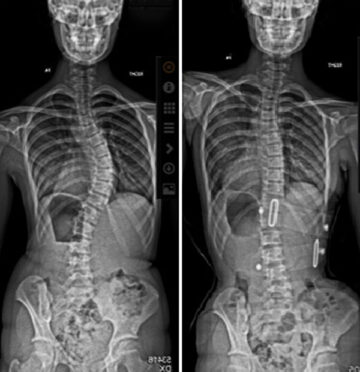

عوامل خفية تحدد نجاح حزام اعوجاج العمود الفقري: ما يجب أن يعرفه كل والد تلعب الدعامات العلاجية (الأحزمة) دورًا أساسيًا في علاج الجنف مجهول السبب لدى المراهقين، خاصة في الحالات المتوسطة التي لا تستدعي

معايير نجاح حزام اعوجاج العمود الفقري: دليل شامل للأهل لتحقيق أفضل النتائج يعاني بعض المراهقين من اعوجاج العمود الفقري المعروف بانحناء العمود الفقري الجانبي، وهو حالة قد تؤثر على شكل الظهر وصحة الجسم مستقبلاً.

العوامل التي تؤثر على نجاح حزام اعوجاج العمود الفقري : كيف تزيد نسبه التصحيح؟ يعاني عدد كبير من المراهقين من اعوجاج العمود الفقري (الجنف)، وهو انحناء جانبي قد يزداد مع النمو. وعندما يصل الانحناء

ما الذي يحدد نجاح حزام اعوجاج العمود الفقري؟ دليلك لفهم عوامل النجاح يُعتبر حزام اعوجاج العمود الفقري (أو دعامة الظهر) من أهم الطرق غير الجراحية لعلاج اعوجاج العمود الفقري عند المراهقين، خصوصًا في الحالات

عوامل نجاح حزام اعوجاج العمود الفقري : اكتشف التفاصيل الصغيرة التي تصنع الفرق الكبير مقدمة اعوجاج العمود الفقري (الجنف) عند الأطفال والمراهقين يُعد من أكثر مشكلات النمو شيوعًا، ويُعتبر الحزام الطبي الوسيلة الأساسية لإيقاف

عوامل تؤثر على نجاح حزام اعوجاج العمود الفقري | أسرار لزيادة فاعلية الحزام يُعتبر حزام اعوجاج العمود الفقري من الوسائل العلاجية الأساسية لعلاج الجنف، خاصة عند المراهقين في مرحلة النمو. وعلى الرغم من أن